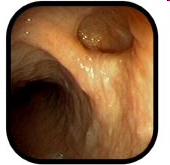

QB-nun orta divertikulu

Həqiqi, traksiyon divertikuldur, QB-nun döş hissəsində, traxeya bifurkasiyasına yaxın bölgədə yerləşir. Kiçik divertikullar adətən əlamətsiz olur, böyük divertikullar isə disfagiya, divertikulit və fistul törədə bilirlər.

Etiopatogenezi

Qazanılmış xəstəlikdir. Divararalığının qranulomatoz xəstəlikləri, adətən vərəm və histoplazmoz limfadenopatiyalarında, həmçinin sarkoidozda QB-nun divarı bitişmələrlə dartılaraq divertikul əmələ gətirir.

Diaqnostikası

Dəqiqləşdirmə

Xəstəliyin dəqiqləşdirilməsi üçün kontrastlı Rentgenoloji müayinə, KT və çox ehtiyatla endskopiya edilməlidir.

- Kontrastlı rentgenoqrafiya - dəqiqləşdirici müayinə üsuludur.

- Endoskopiya - divertikulun perforasiyası təhlükəsinə görə çox ehtiyatla aparılmalıdır.